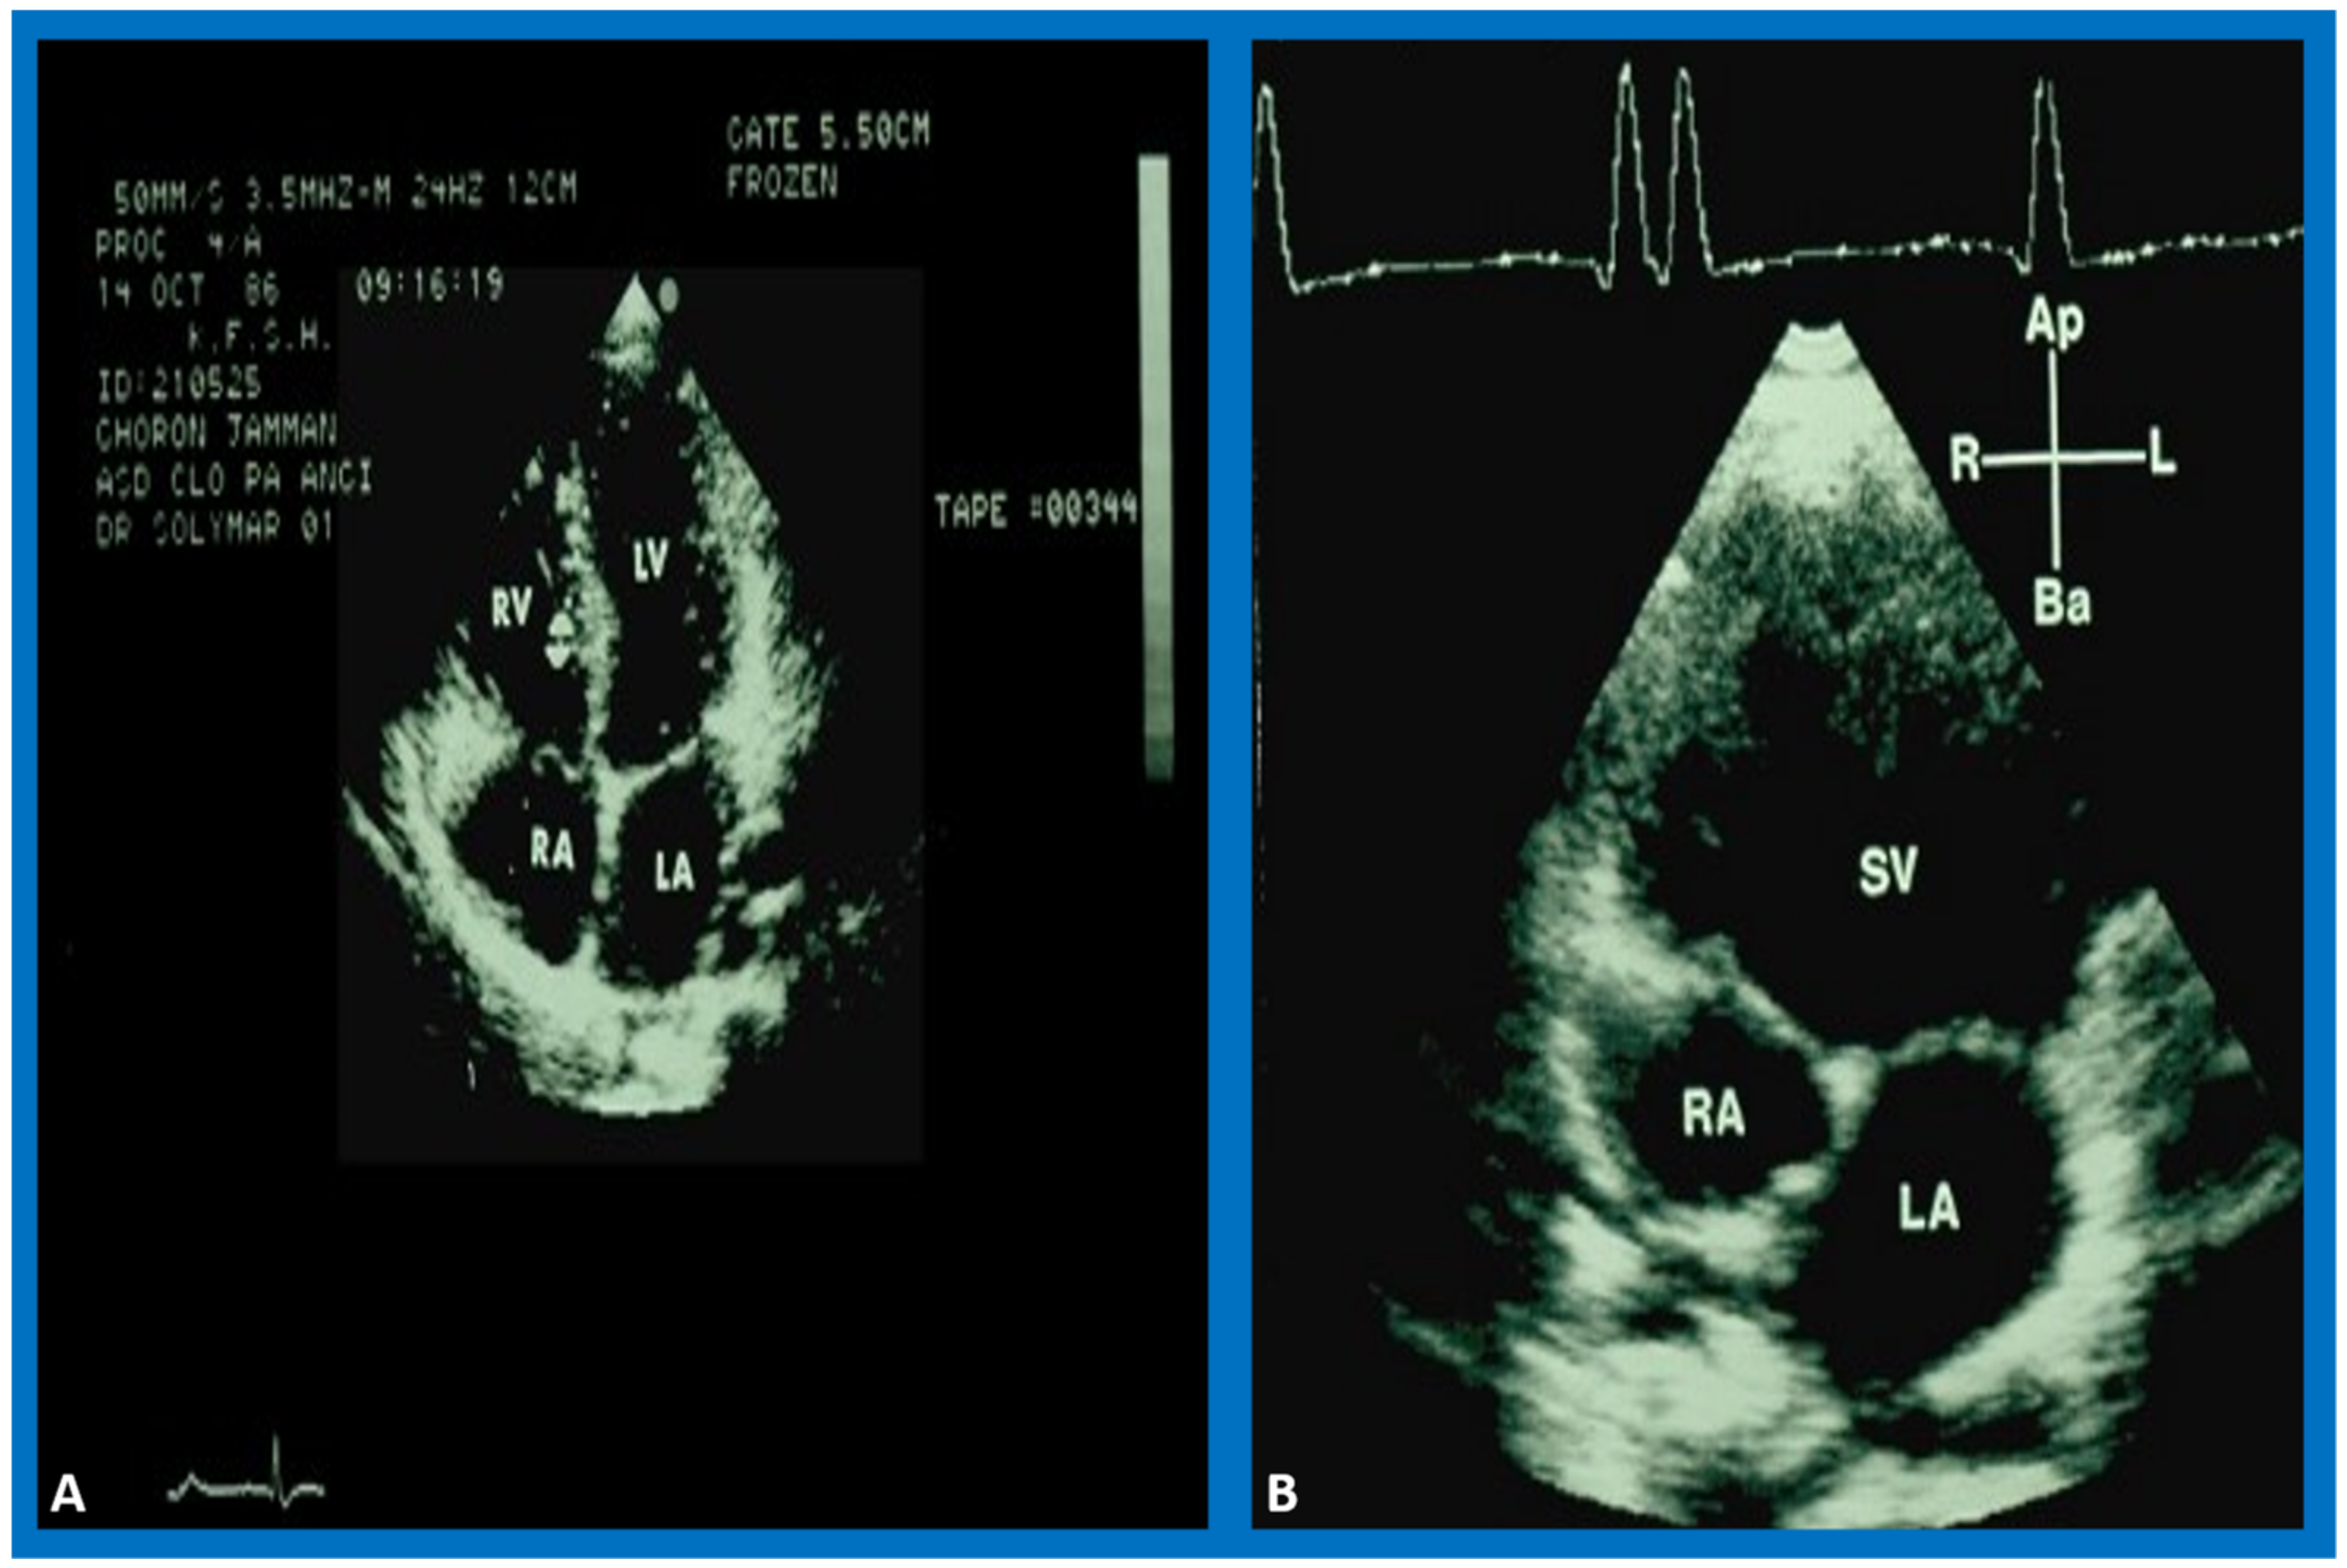

7. Echocardiogram